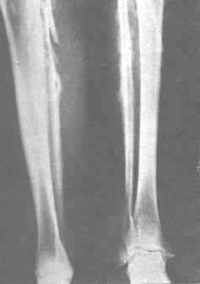

1.慢性氟中毒在成人中主要为不同程度的骨质硬化,晚期可非常明显。骨质硬化可涉及全身,以脊柱髂骨、骼骨以及肋骨较为常见,也见于四肢长骨松质骨的增生硬化使骨小梁增粗,继而髓腔缩小以至消失。骨膜增生可使骨边缘不平,并有增大或增粗现象。

3.氟骨症骨骼除有增生硬化外,亦可有骨质疏松、软化、生长障碍线、关节退变等不同的病理改变和X线征象。